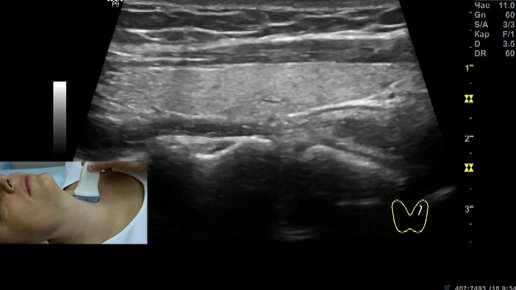

Как делают УЗИ щитовидной железы